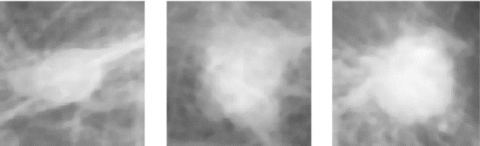

Figure 2(a) – 2(c) is an input mammographic image which is already filtered images of mass types that are restricted, conjecture or distracted. The real input mammogram images were obtained from the universal available Image Analysis Society's database (MIAS). After the noise and artifact sources had been removed, the pectoral part of muscles from the image was removed by the seed growing technique such as contour growing, histogram thresholding and edge detection [7-9]. The defined method is perfect and completely computerized. To check mammography images of different densities are examined using this model. In left side images the pectoral can be present at the upper left, also for right oriented images it is in the upper half of the images, because of this position all the images are rotated to the left side prior to the application of seed growing procedure. A threshold (th) value is calculated and set, the window from the image is set into the left corner of the upper side also slid in the right side in anticipation of pixels sum exceeds the threshold value. At last, execution of the algorithm stops while the window reaches bottom of the image. After that, in order to form a straight line, the area between the Pecs is smoothed. Figure 2(d), 2(e), and 2(f) illustrate images obtained after the pectoral muscles were removed in the three cases studied.

Figure 2. MIAS mammography image behind noise and label removal